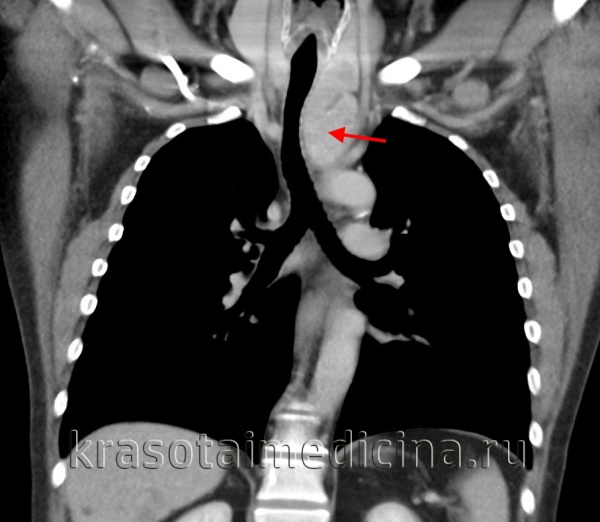

Рентгенологическое исследование: срединная тень почти на всем своем протяжении расширена в обе стороны за счет патологического затемнения, занимающего большую часть переднего средостения. Это интенсивное, неоднородное затемнение имеет дольчатую форму с бугристыми четкими контурами, расположенными местами (справа) в виде «кулис». На жестком снимке с передержкой и на томограммах более отчетливо выявляется дольчатый характер патологического образования и узлы, расположенные на различной глубине, видны также неизмененные трахея и главные бронхи. Пищевод не изменен.

Очаговых и инфильтративных изменений в легких не определяется. Куполы диафрагмы подвижны, синусы свободны. Корни легких, сердце и аорта не определяются из-за наложения на них описанного затемнения.